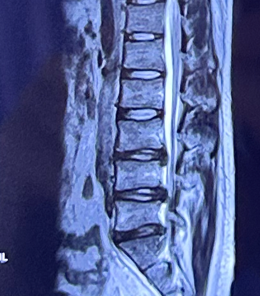

患者小张腰痛伴左下肢小腿外侧疼痛麻木4年,严重影响生活,慕名到省立医院脊柱外科崔新刚教授处就诊,崔新刚教授仔细检查后确诊为腰椎间盘突出症,需要手术治疗。

针对患者年纪轻需要尽量保留活动节段的情况,崔新刚教授确定为患者实施OBE内镜下髓核摘除术,去除椎间盘突出髓核解除疼痛。同时,因患者体重较大,髓核摘除术后突出复发风险要高于其他人。崔新刚教授决定在OBE内镜下髓核摘除后行纤维环缝合术,降低患者术后复发风险。仅用时不足1小时,崔新刚教授顺利完成OBE髓核摘除术+纤维环缝合术。术后患者疼痛解除。